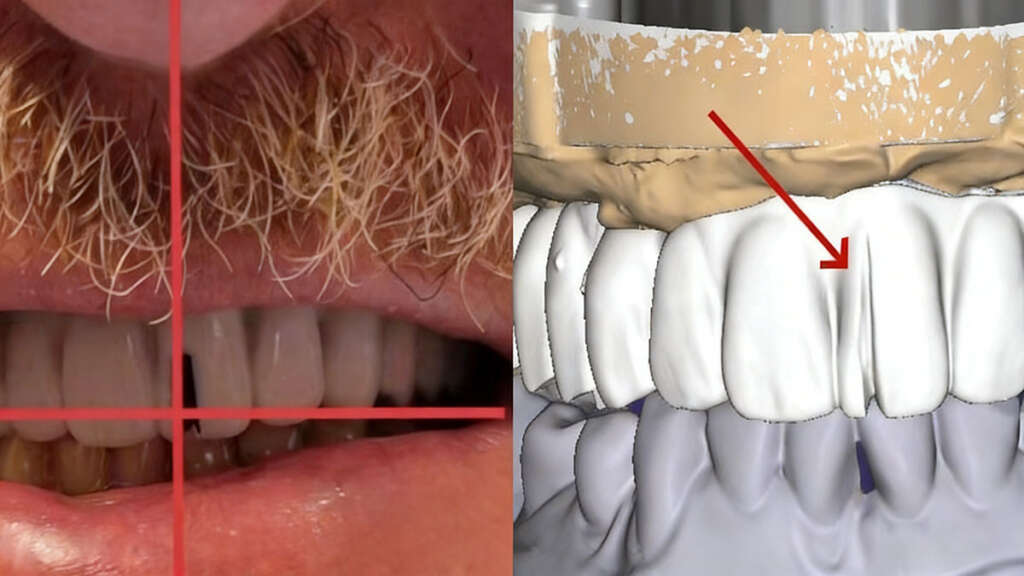

Adjust the midline for the implant case

About 10 days later, the dentists tried fitting and bite. The fitting and bite were great, but the mid-line required adjustment. The dentist marked a new midline and took some pictures. Then our customer shipped everything back to us, including the 3D printed models, the aluminum bar, the 3D printed bridge, and a new bite registration. We also received pictures with the correct mid-line.